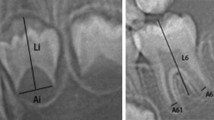

Using a large radiological database of 3605 orthopantomograms (1734 females and 1871 males) of healthy French patients aged between 2 and 24 years, seven left permanent mandibular teeth and the 4 third molars were assessed using Demirjian’s stages. Dental age estimation was then performed using Demirjian’s reference method and various ML regression methods. Two analyses were performed: with the 7 left mandibular teeth without third molars for the under 16 age group and with the third molars for the entire study population. The different methods were compared using mean error, mean absolute error, root mean square error as metrics, and the Bland-Altman graph.

Demirjian A, Goldstein H, Tanner JM (1973) A new system of dental age assessment. Hum Biol 45:211–227

Demirjian A, Goldstein H (1976) New systems for dental maturity based on seven and four teeth. Ann Hum Biol 3:411–421. https://doi.org/10.1080/03014467600001671